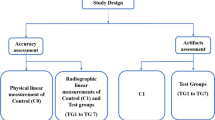

This study compares reduction of strong metal artifacts from large dental implants/bridges using spectral detector CT-derived virtual monoenergetic images (VMI), metal artifact reduction algorithms/reconstructions (MAR), and a combination of both methods (VMIMAR) to conventional CT images (CI).

Forty-one spectral detector CT (SDCT) datasets of patients that obtained additional MAR reconstructions due to strongest artifacts from large oral implants were included. CI, VMI, MAR, and VMIMAR ranging from 70 to 200 keV (10 keV increment) were reconstructed. Objective image analyses were performed ROI-based by measurement of attenuation (HU) and standard deviation in most pronounced hypo-/hyperdense artifacts as well as artifact impaired soft tissue (mouth floor/soft palate). Extent of artifact reduction, diagnostic assessment of soft tissue, and appearance of new artifacts were rated visually by two radiologists.

Visual analysis

Visually, the extent of artifact reduction and diagnostic assessment of soft tissue (mouth floor, soft palate, and buccal soft tissue) was rated on 5-point Likert scales while the appearance of new artifacts was indicated on a tertiary scale by two radiologists with 2 and 3 years of experience in oncologic imaging, as described in Table 1. Additionally, both readers reported the optimal keV values for diagnostic assessment (artifact extent versus introduction of new artifacts and loss of soft tissue contrast).

The two readers further assessed the subjective image quality of CI, MAR, VMI, and VMIMAR. For VMI and VMIMAR, we chose reconstruction levels with greater increment (70 keV, 100 keV, 140 keV, and 200 keV) to allow for the detection of relevant changes and not to obscure differences by repetitive rating of too similar images. Following parameters were used: slice thickness 1 mm, axial plane, and soft tissue window settings. Further, readers were explicitly free to adjust window settings manually.

Statistical analysis

JMP software (JMP v12, SAS Institute) was used for statistical analyses. Quantitative results are displayed as mean (± standard deviation), and qualitative results are displayed by count and percentage. The Shapiro-Wilk test was applied to test for normal distribution. For further testing, the Wilcoxon test with steel adjustment for multiple comparisons was applied. Statistical significance was set to p < 0.05. The intraclass correlation coefficient (ICC) for visual analyses was assessed and interpreted as proposed earlier [23, 24].